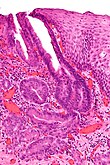

Esophageal inlet patch

General

- Benign and likely not of any significance.[13]

Gross

- Proximal esophagus - salmon coloured lesion.[13]

Microscopic

Features:

- Gastric mucosa.[14]

Image:

Esophagus at 22 cm, Biopsy:

- Gastric type mucosa with mild chronic inactive inflammation, see comment.

- Scant unremarkable squamous epithelium.

- NEGATIVE for intestinal metaplasia.

- NEGATIVE for dysplasia.

Comment:

This is in keeping with an "inlet patch", also known as "heterotopic gastric mucosal patch of the proximal esophagus".